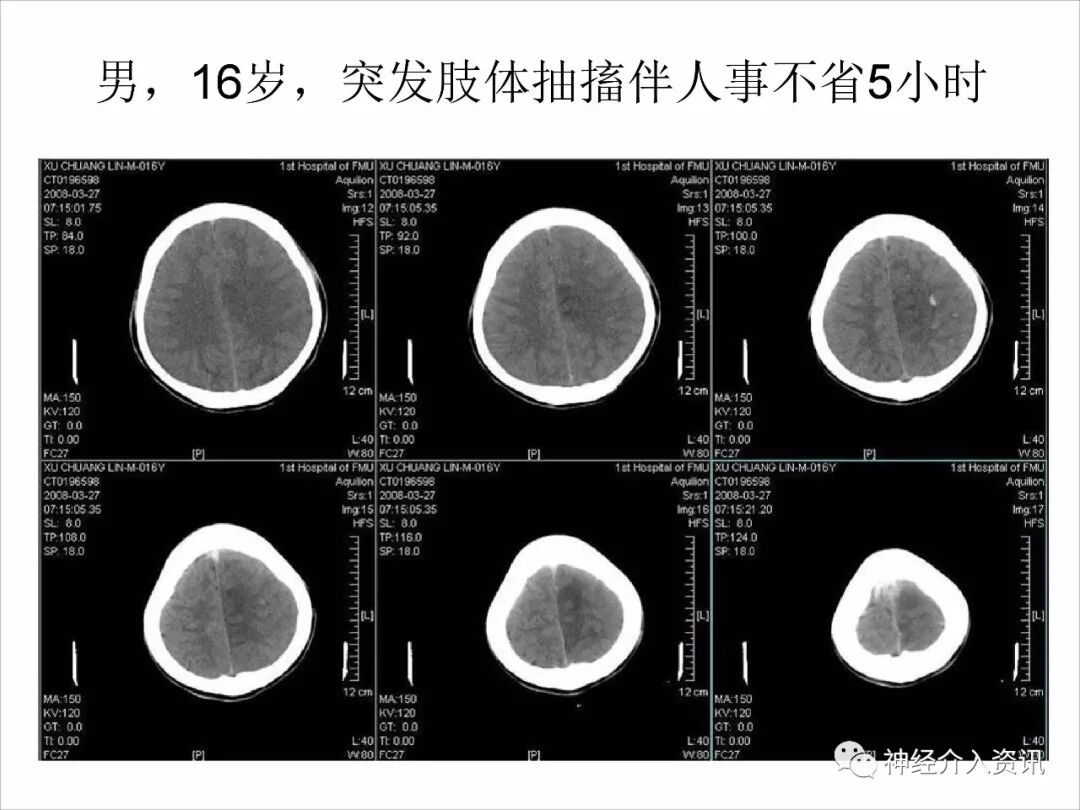

今天为大家分享的是由福建医科大学附属第一医院戴琳孙教授在第十二届华东地区脑血管病血管内治疗大会上带来的“脑静脉窦血栓的血管内治疗”精彩讲课视频和PPT,欢迎观看!(内容未经讲者审核,不当之处请与我们联系)